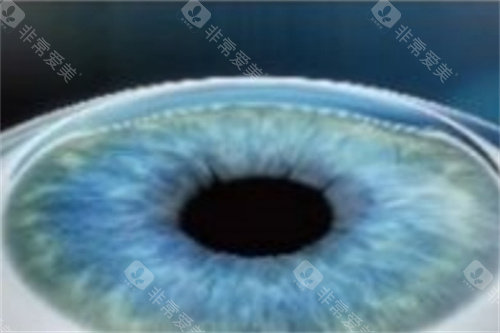

全飞秒激光手术:15800元/双眼